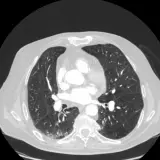

Des cas entièrement interactifs avec les outils attendus d'un PACS — défilement, fenêtrage, zoom, déplacement, mesures, ROI et mode plein écran.

Des annotations détaillées mettent en évidence les résultats clés directement sur les cas. Cliquez sur les résultats liés dans les descriptions de cas pour accéder à leur emplacement exact sur l'examen.

Défilez, déplacez, fenêtrez et zoomez comme sur une station PACS de travail